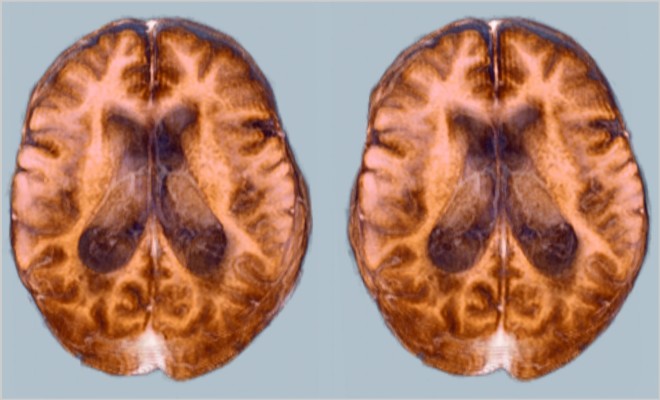

Первичное обследование включает выявление внешних признаков инсульта: ассиметричность лица, нарушение речи, паралич конечностей. Врач проверяет внутриглазное давление и неврологические нарушения. Наиболее результативной диагностикой считается магнитно-резонансная томография и КТ.